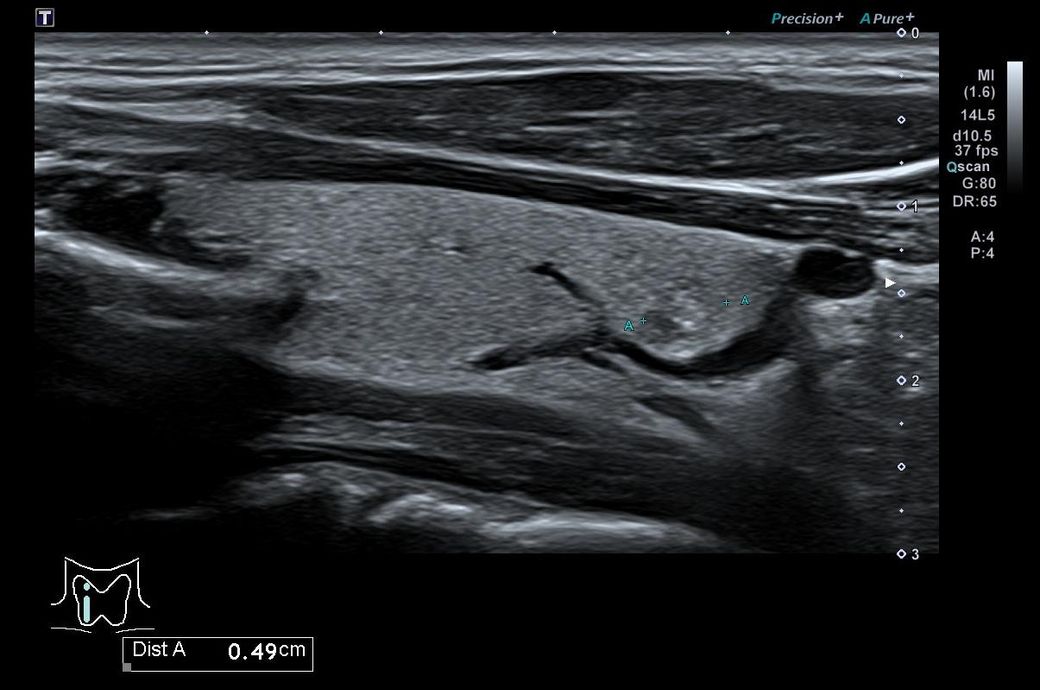

갑상선 초음파인데 모양이나 위치가 안좋나요?

건강검진을 했는데 갑성선 우엽에 0.5cm 석회포함결절 이라고 하는데

위치나 상태가 안좋은 편일지요?

• 2번 째 사진